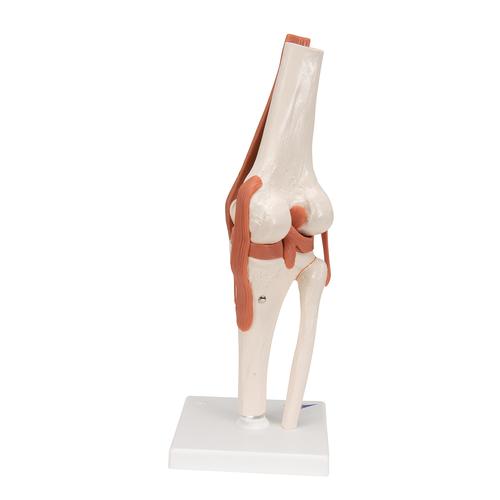

Functional human knee joint model with ligaments

This high quality, life-size functional knee joint model clearly shows the anatomy and mechanics of the knee joint. This fully flexible knee joint model demonstrates abduction, anteversion, retroversion and internal/external rotation. Delivered on removable stand for easy study or display.